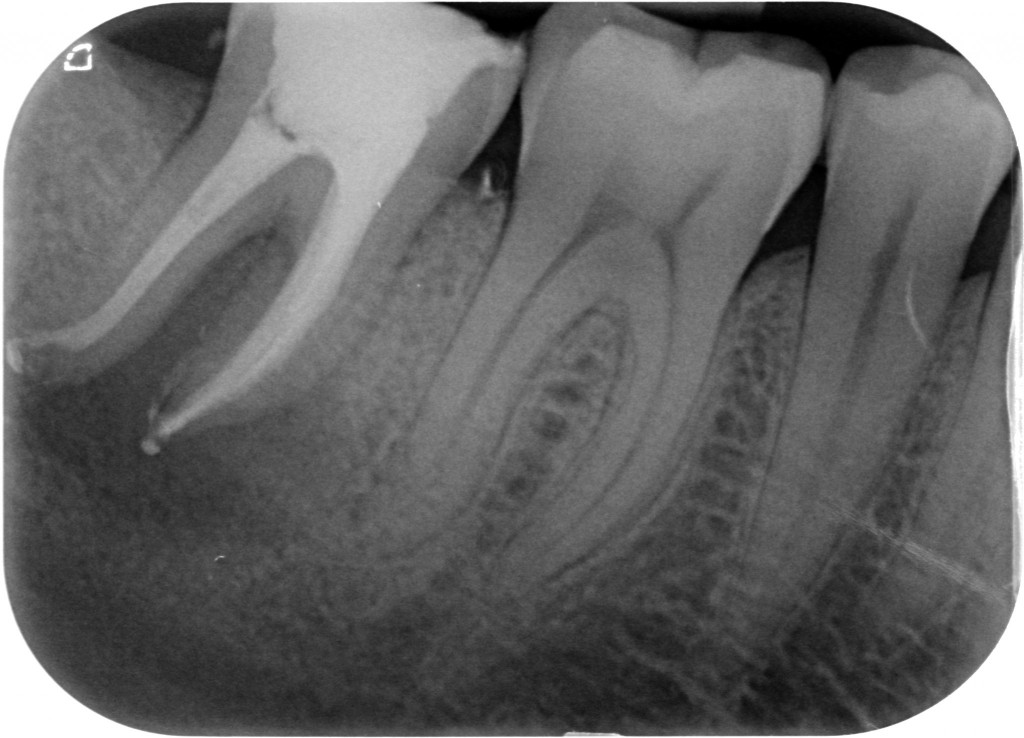

Da allora su 48 primi molari ho trovato il canale mesiale-mediano 24 volte in 17 mesi! Percentuale di 50%!!!

E sto tenendo il conto solamente dei primi molari, ma come vedrai qui sotto, li trovo anche sui secondi molari inferiori.

La scoperta che il canale mesiale-mediano deve essere cercato ed è spesso presente ha dato una soluzione a questi casi che mi capitano con una certa frequenza. Canali della radice mesiale del primo molare inferiore chiusi in apparenza bene con lesione. Il mio socio che si occupa quasi solo di chirurgia continuava a dirmi che poteva essere un problema di detersione, ma io a questo non ho mai creduto. Se un canale chiuso radiograficamente bene ha una lesione o è fratturato in verticale o manca un canale.

In questi casi avverto il paziente delle due ipotesi e appena arrivo a pulire la camera provo subito con impazienza a cercare il canale mancante. E c’è quasi sempre.